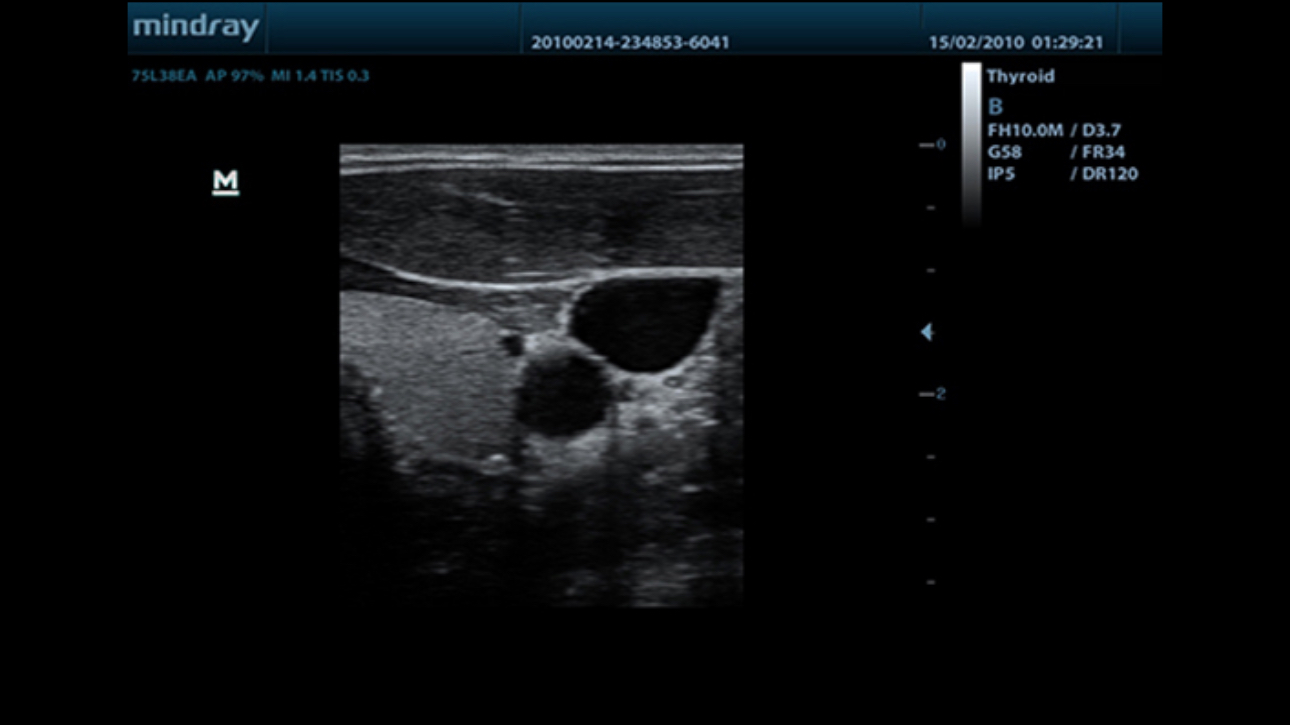

iBeam?

Permits use of multiple scanned angles to form a single image, resulting in enhanced contrast resolution and improved visualization